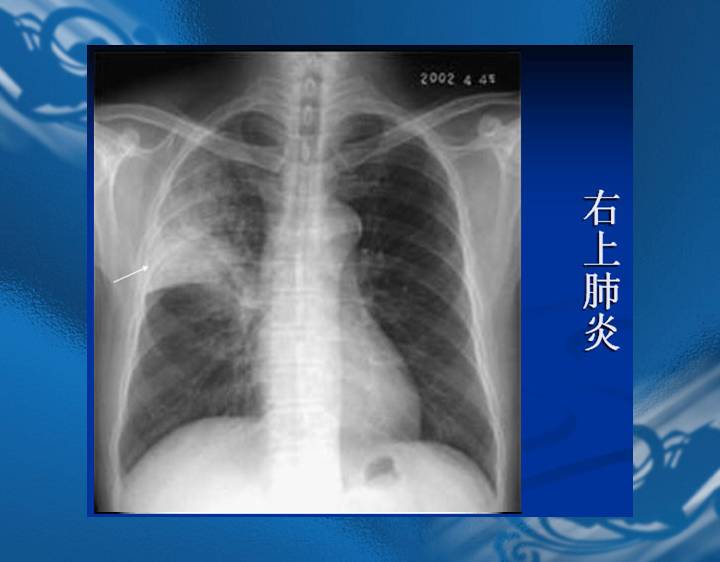

执业医师资格考试“实践技能”影像学辅导资料